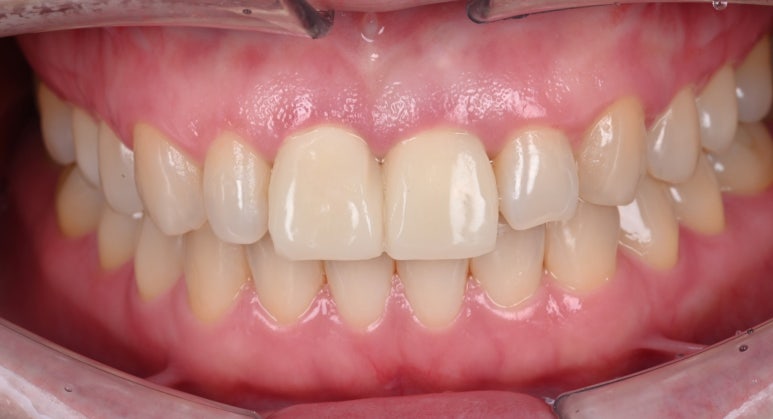

30대 여성 환자분께서 앞니 크라운 때문에 내원해주셨습니다.

오래전 타치과에서 가운데 앞니 두 개에 신경치료와 크라운 치료를 받으셨는데,

시간이 지나면서 잇몸이 내려가 내부 치아가 드러난 상태가 되었고,

심미적으로 만족스럽지 않다고 하셨습니다.

25.09.11 치료 후